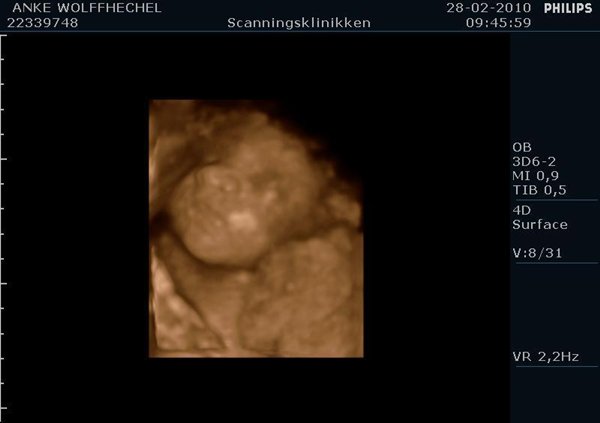

Men det hjalp åbenbart, for madammen var i et helt andet humør den dag. Hun viste sig fint frem, lå og grinede, smilede og lavede kyssemund til den store guldmedalje. Sikke en oplevelse!

Jeg har vedlagt et par billeder, et af kønnet i 2d, og nogle af vores fine pige med den søde knoldenæse og de store kinder. (Næsen er i øvrigt ikke så stor i virkeligheden, den ser kun sådan ud, fordi den optages lige forfra

)